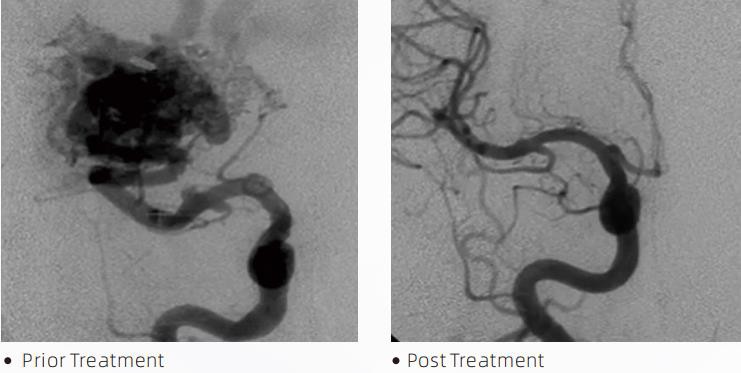

ЛаватаТМLiquid Embolic System е интервенционална ендоваскуларна терапия за лечение на мозъчно-съдови малформации. Цереброваскуларна малформация се отнася до група от доброкачествени или злокачествени невроваскуларни аномалии, които могат да доведат до вътречерепен кръвоизлив, мозъчен инфаркт, церебрална исхемия и други заболявания. Системата за течна емболизация е медицинско устройство, прилагано чрез просто вътресъдово вмъкване, което емболизира необичайни церебрални кръвоносни съдове чрез инжектиране на специален течен материал. Течният материал образува контролирана тъканна емболия в кръвоносните съдове, което може да намали въздействието на цереброваскуларните малформации върху пациентите. Микрокатетър за доставяне, съвместим с DMSO, който е показан за използване в невроваскулатурата, се използва за достъп до мястото на емболизация. Lava течен емболичен агент е неадхезивна течна емболизираща агентна система, състояща се от съполимер EVOH (етилен винилов алкохол), разтворен в DMSO (диметилсулфоксид), и суспендиран микронизиран танталов прах за осигуряване на контраст за визуализация при флуороскопия. ЛаваTMсе предлага в три продуктови формули, LAVA-12, LAVA-18 и LAVA-34. LAVA-12: Препоръчва се при захранване на дистални микросъдове и чрез малки хранилки. LAVA-18: Препоръчва се, когато инжектирането на педикула при хранене ще се извършва близо до гнездото; LAVA-34: Препоръчва се за емболизиране на по-висок поток и по-големи фистулни компоненти.